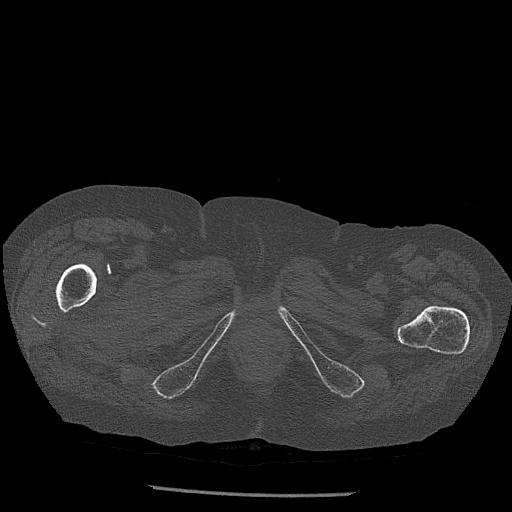

100703 1/27 両股正面+軸 1/29 両股正面+軸 94歳女性 パンソンロン

46666 1/28 両股正面+軸と 1/26 右手関節 2R 76歳女性 右転子部骨折

37 1/18 両股正面+軸 1/22 2R 86歳女性 右転子下

82084 1/14 1/20 股関節 2R 78歳男性 右人工骨頭

102811 1/13 股関節 2R 1/19 2R 80歳女性 右DHS

91569 3/25 両股正面とラウエン 70歳女性 人工骨頭+バンクーバー